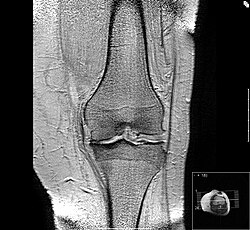

Magnetska rezonancija

Tradicionalni način postavljanja dijagnoze artroze predviđa pojavu trajne i uporne boli i ukočenosti i otkrivanje oštećenja hrskavice u zglobovima na rendgenskoj slici. Prisutnost boli sugerira da je od početka bolesti prošlo dosta vremena, pa su oštećenja u zglobu obično teška. Liječenje se u tom trenutku usmjerava samo na ublažavanje simptoma. U težim je slučajevima za potpuno oslobađanje tegoba potrebna i potpuna zamjena oboljelog zgloba umjetnim zglobom.

Uvođenjem magnetske rezonancije (MR) i primjenom novih metoda snimanja tom tehnikom ostvaren je izuzetan napredak u ranom otkrivanju i prevenciji artroze. Kod artroze se primjenjuje nova metoda snimanja magnetskom rezonancijom kojom se određuje koncentracija molekule glikozaminoglikana (GAGS) u hrskavici zgloba. Glikozaminoglikani daju mnoga mehanička svojstva hrskavičnom tkivu, uključujući i njegovu čvrstoću i elastičnost. Jedna od činjenica koja se danas primjenjuje u dijagnostici je ta da se koncentracija GAGS smanjuje u hrskavici zahvaćenoj artrozom. Razlozi smanjenja su nepoznati.[43]